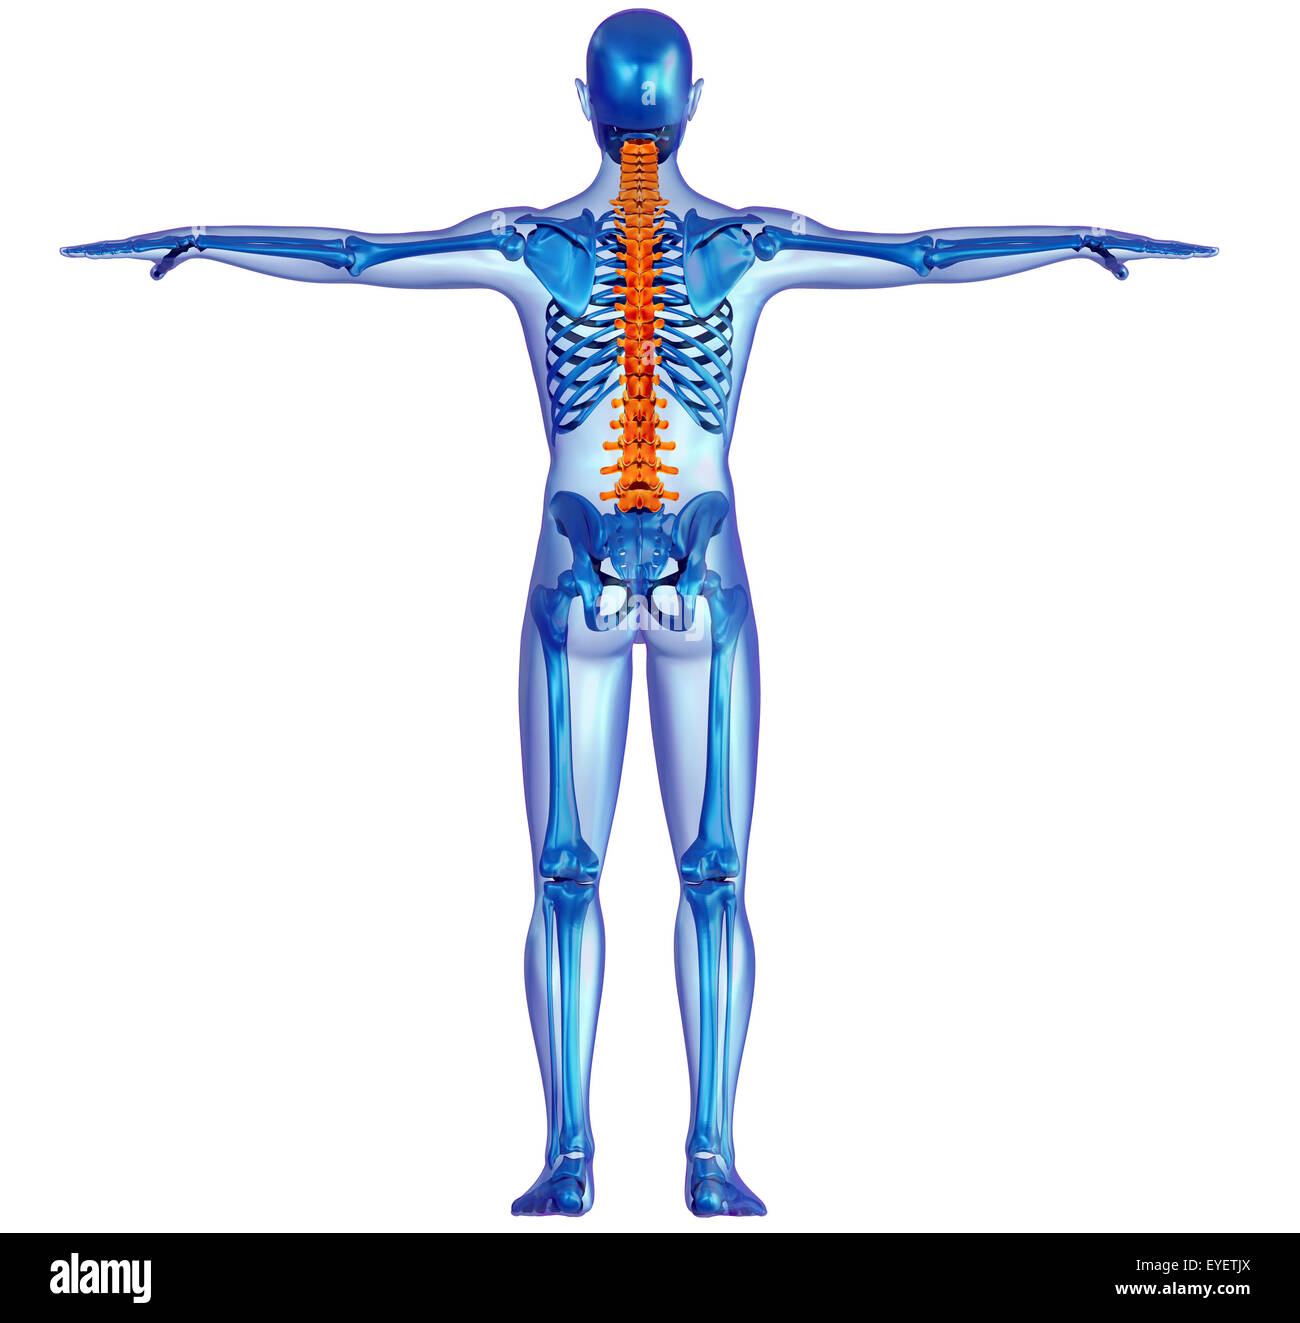

Back view x-ray of a human body and skeleton with highlighted spine …

The Human Body By X-rays On Blue Background. Stock Illustration …